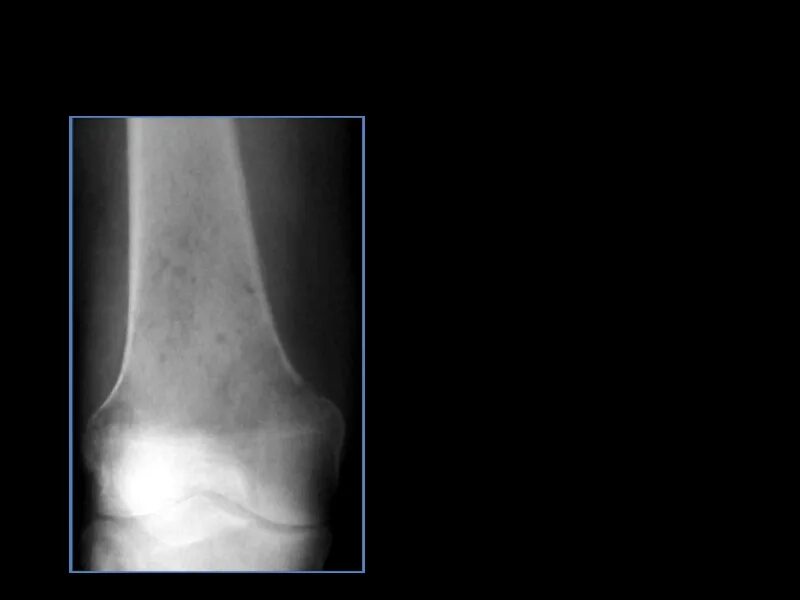

Зона деструкции